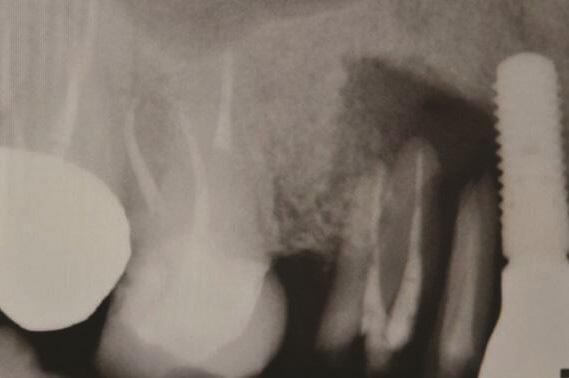

Пациент 2: Здоровый пациент мужского пола 63 лет обратился с имплантатом № 1.3, у которого диагностирован РПИ, на который повлиял ранее эндодонтически леченный и сломанный зуб № 1.4 (Фото 3 и Фото 4). Глубина зондирования вокруг имплантата составляла от 4 до 10 мм (Таблица 1), причем наиболее серьезная потеря кости наблюдалась с дистальной стороны имплантата № 1.3 (Фото 3 и Фото 4).

Фото 3 и Фото 4. Случай 2: Первоначальная клиническая картина, показывающая имплантат № 1.3 с РПИ, на который повлиял сломанный зуб № 1.4 (Фото 3); рентгеновский снимок, показывающий сломанный зуб № 1.4 с периапикальным поражением, распространяющимся на дистальную сторону имплантата № 1.3 (Фото 4).